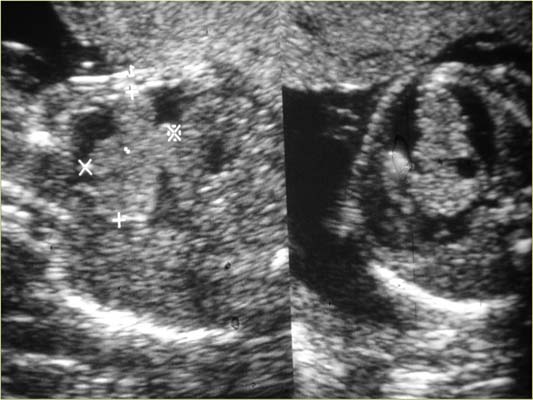

Tératome intra-péricardique 22w